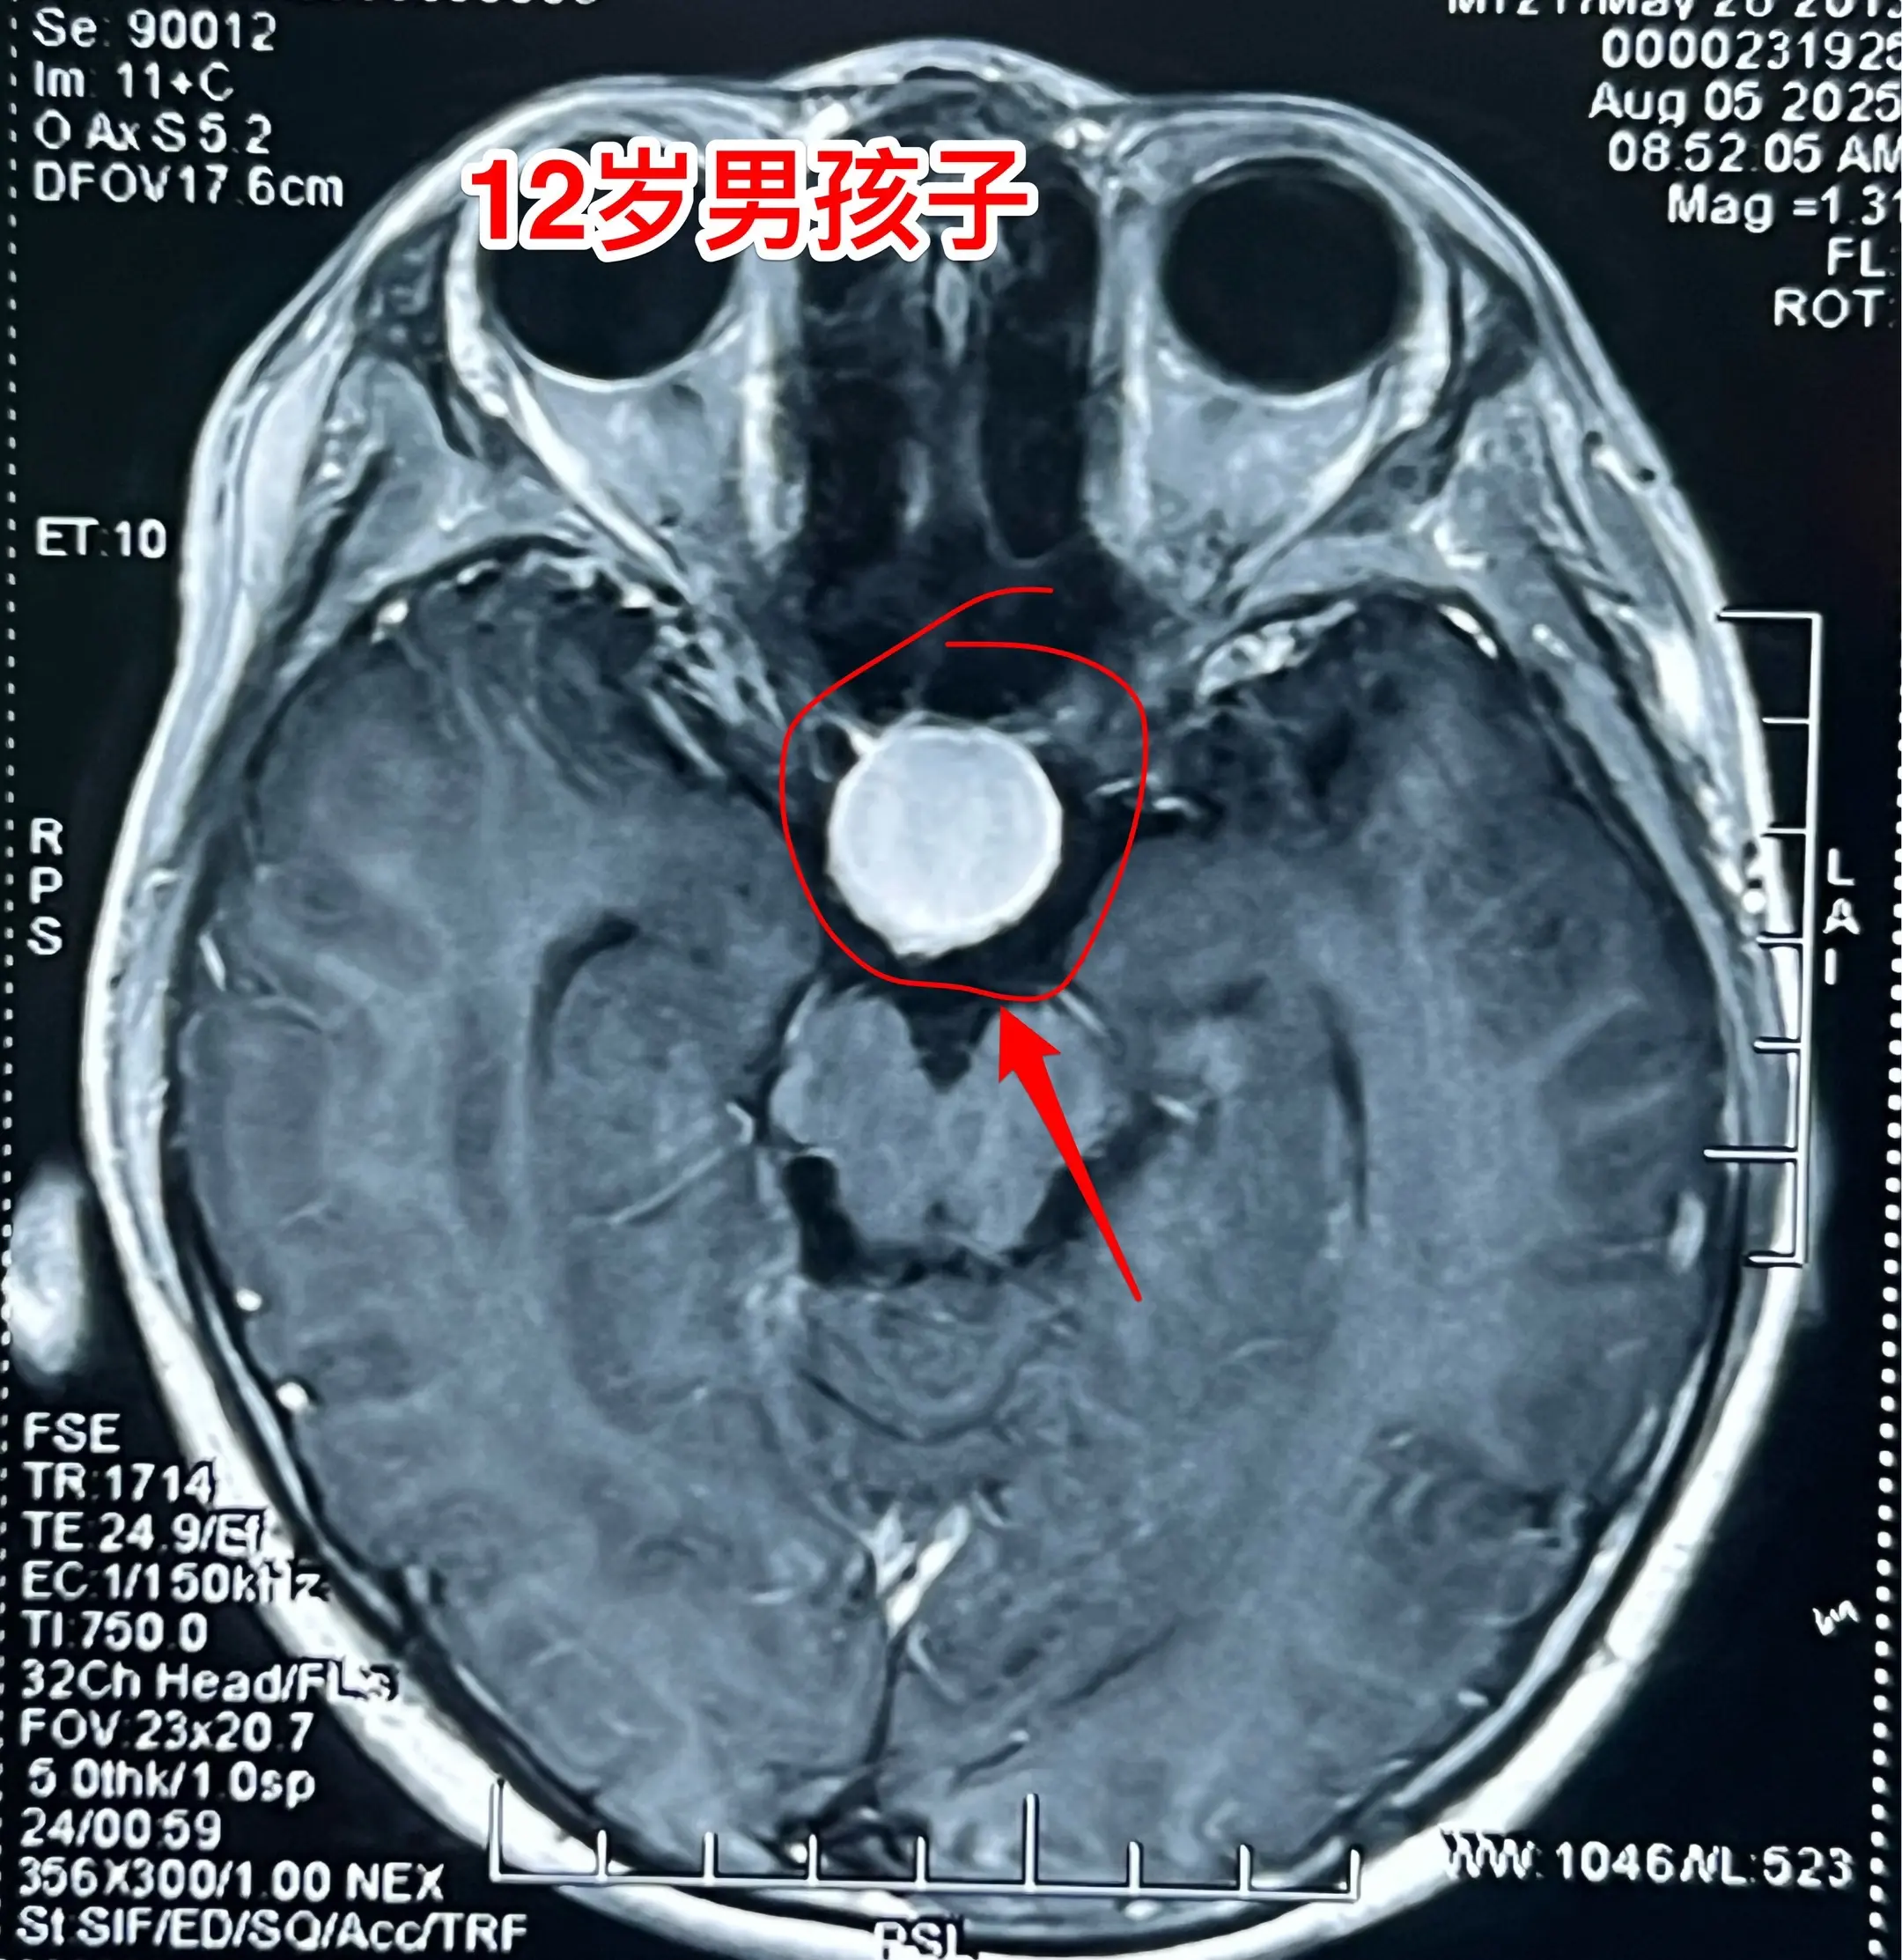

12岁男孩子,视力差、身高增长缓慢。12岁男孩子,视力下降、身高增长缓慢。头CT及MRI显示为典型的造釉型颅咽管瘤。2025年8月7日作了开颅手术。 根据术前的CT和MRI无法判断出垂体受压程度、能否保留垂体和垂体柄。 手术中发现垂体受肿瘤压迫成薄片状,如同饺子皮。好在肿瘤与垂体粘连不紧,经过细心分离,将肿瘤完全切除,同时垂体柄-垂体保留约90%(垂体前叶和后叶均保留)。 这样保留垂体柄和垂体是有意义的,可以减少垂体危象的发生。